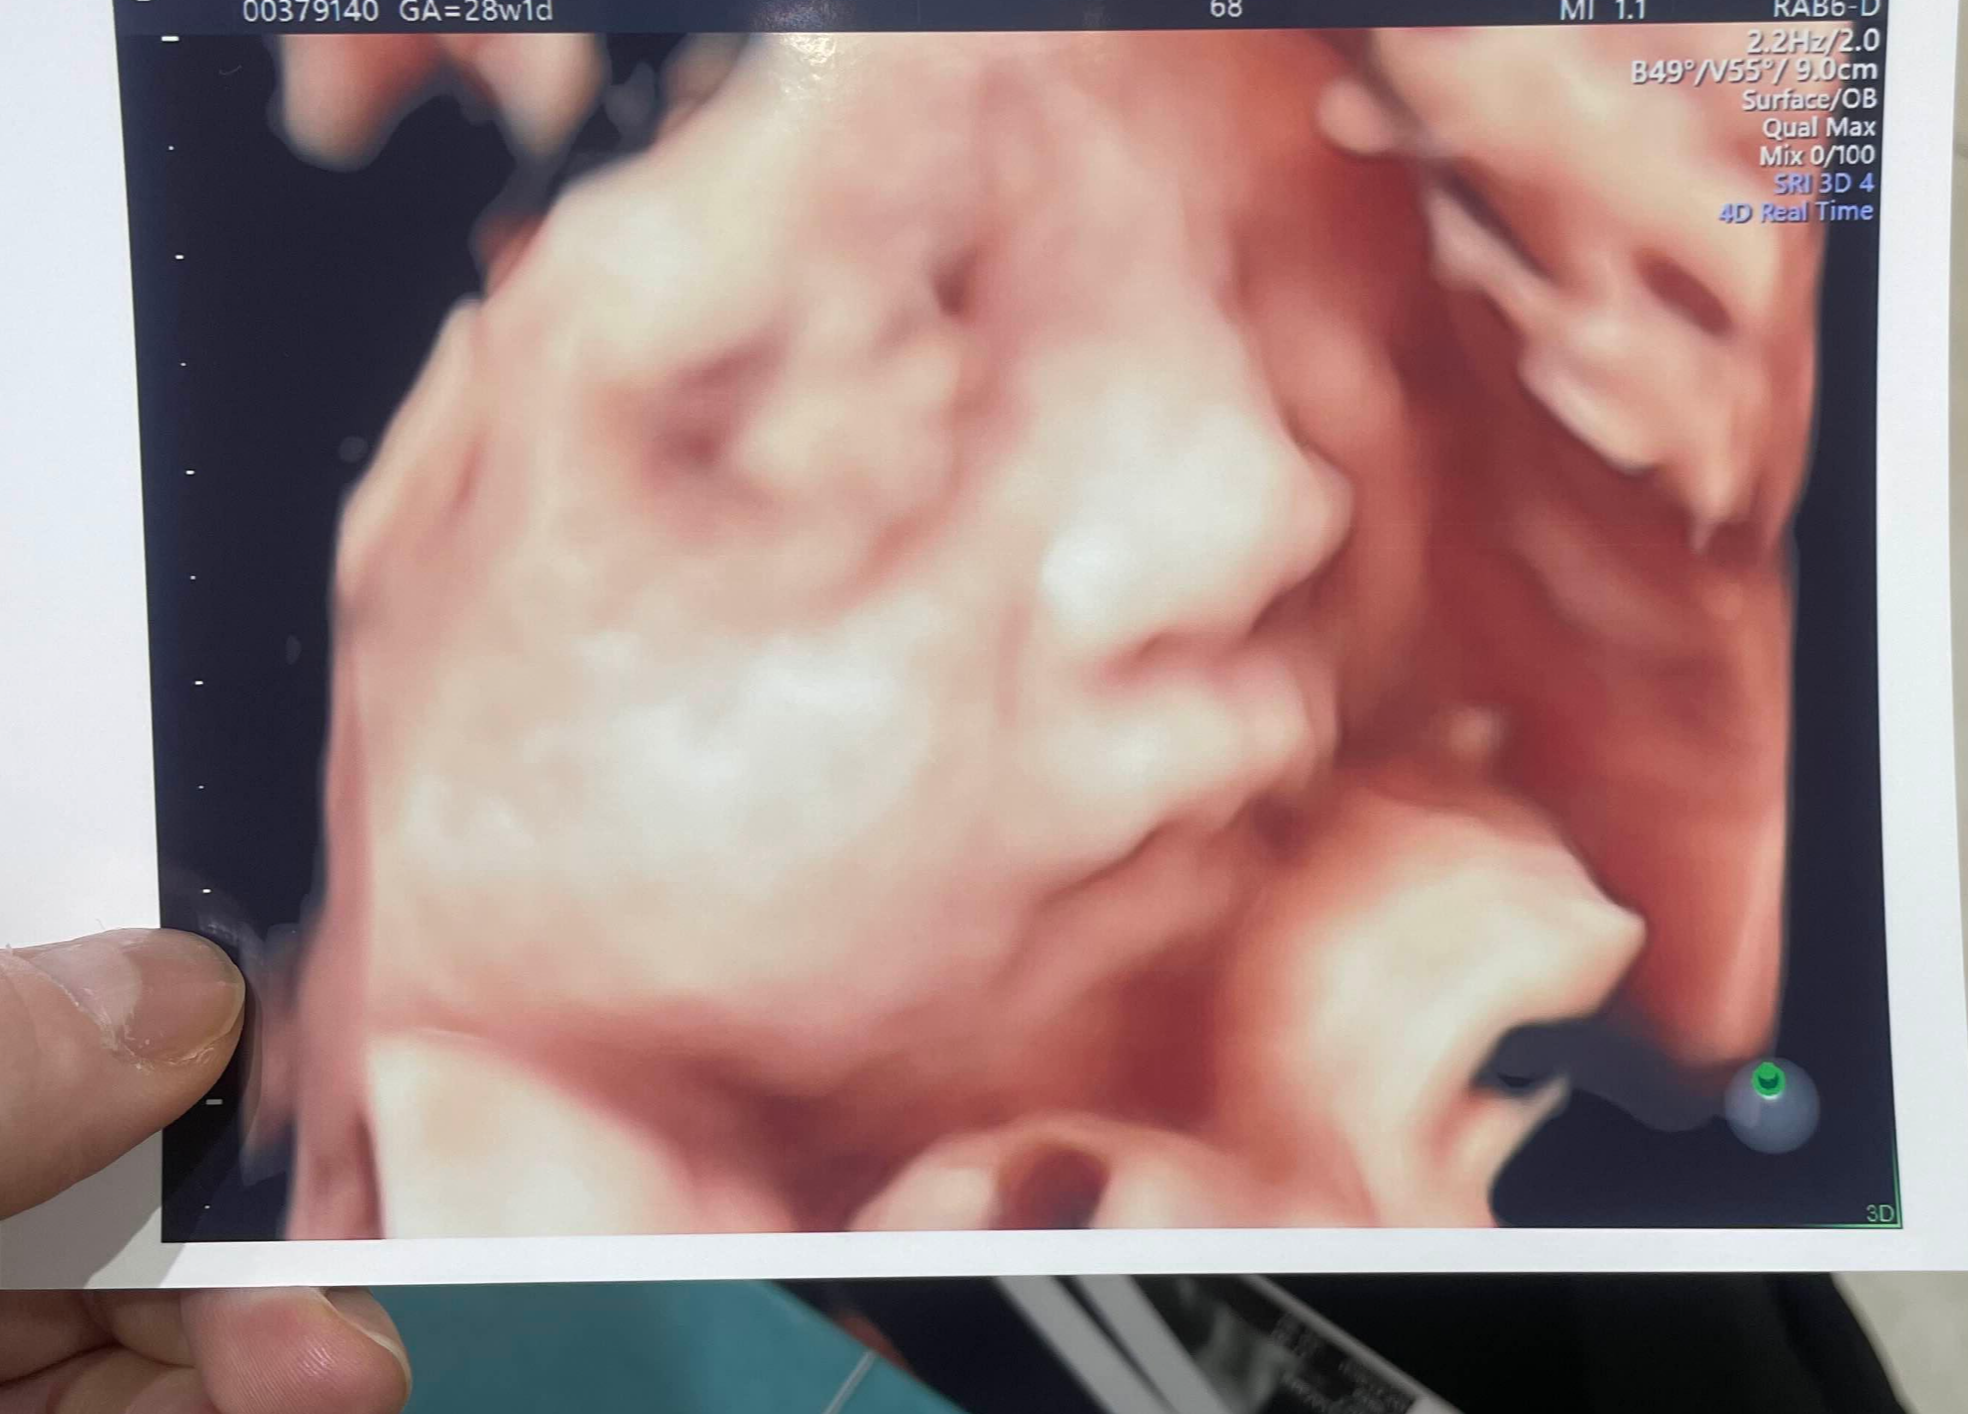

오늘은 아기 얼굴 정밀초음파 보러 가는날이당

얼마나 기다렸던지 시간이 후루룩 가는구만

우리 복복이가 잘 움직여주고 얼굴 보여주지

촘파는 잠시 대기하고 바로 봐주셨다.

우리 아가 많이 컸구나

울 복복이 아빠 많이 닮았네.. ^^;

손가락 발가락도 한번씩 다 봐주시고!

너무 귀여운 것..

오늘 샘이 재대로 찍어주신다고 복복이를 막 엄청 세게 눌러서

ㅋㅋㅋㅋㅋ 복복이가 막 입도 벌리고 눈도 뜨고 너무 구엽..

언제 이렇게 무럭무럭 자랐데 엄마는 너무 고맙당 열심히 자라줘서

매일매일 엄마뱃속에서 꼬물꼬물 열심히 커주느라 고생이 많지🤍